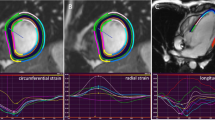

All images (CMR, CT and TTE) were analyzed by one observer (A.T.),who had 6 years of experience in cardiovascular imaging, in a random order and blinded to the results of the other image modalities. The TTE, CT, and CMR data was then re-measured by a second observer (S.Y.), who has one year of experience, blinded to the results of the first observer and to the corresponding measurements of the other modalities. For 2D TTE, speckle tracking analysis was performed using dedicated commercially available software (2D Cardiac Performance Analysis, Tomtec Imaging Systems). End-systolic and end-diastolic frames were identified manually; additionally the annulus and apex were identified manually in end-systole (Fig. 1). Subsequently, the software semi-automatically detected the end-diastolic and end-systolic myocardial contours. These contours were visually checked and corrected if necessary. This process was performed in all apical views (A2ch, A3ch, and A4ch).

Left ventricular parameters by three different modalities in the same patient. TTE Transthoracic Echocardiography, CT Computed Tomography, CMR Cardiovascular Magnetic Resonance, EDV end-diastolic volume, ESV end-systolic volume, EF Ejection Fraction, GLS Global Longitudinal Strain. Yellow lines depict GLS during the cardiac cycle. eS end-systolic phase, eD End-diastolic phase

All CT and CMR images were analyzed semi-automatically using commercially available software from Medis Medical Imaging Systems, Leiden The Netherlands. All images were loaded into the Medis Suite software (version: 3.1.16.6). A2ch, A3ch, and A4ch reconstructions were made from the 3D data sets using Medis 3D View (version: 3.1.18.1). For the CMR analysis only the magnitude images, which contain the anatomical data, of the 4D flow data set were used. All cardiac phases were included in the multi-plane reconstructions and endocardial contours were drawn manually at both end-diastole and end-systole using Medis QMass software (version: 8.1.30.4) where the papillary muscles and trabeculations were included in the LV lumen. Subsequently GLS, ejection fraction (EF), end-diastolic and end-systolic volume (EDV and ESV) were calculated using QStrain software (version: 3.1.16.6). Volumes were corrected for body surface area (BSA). BSA was calculated according to the Dubois formula [25]. In QMass LV contours were drawn manually and focused on adequate tracking of the myocardium for precise strain analysis. However, changes to the contours necessary for optimal tracking of the myocardium caused an underestimation of the ESV. Therefore, in order to provide data on the inter-modality variability of the volumes, a second set of separate endocardial contours had to be drawn for the measurement EDV, ESV and EF. The second trace of endocardial contours, drawn for the volumetric analysis, used standard anatomical landmarks (Supplemental Video 1). However, for adequate strain analysis the left ventricular outflow tract (LVOT) had to be excluded, and the first trace therefore started more apically in both end-systole and end-diastole, (Supplemental Video 2) to prevent highly positive segmental strain disturbing GLS measurement. For the inter-observer variability, twenty patients were chosen at random.